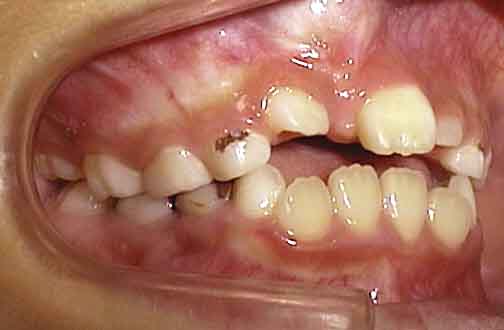

初診の状態